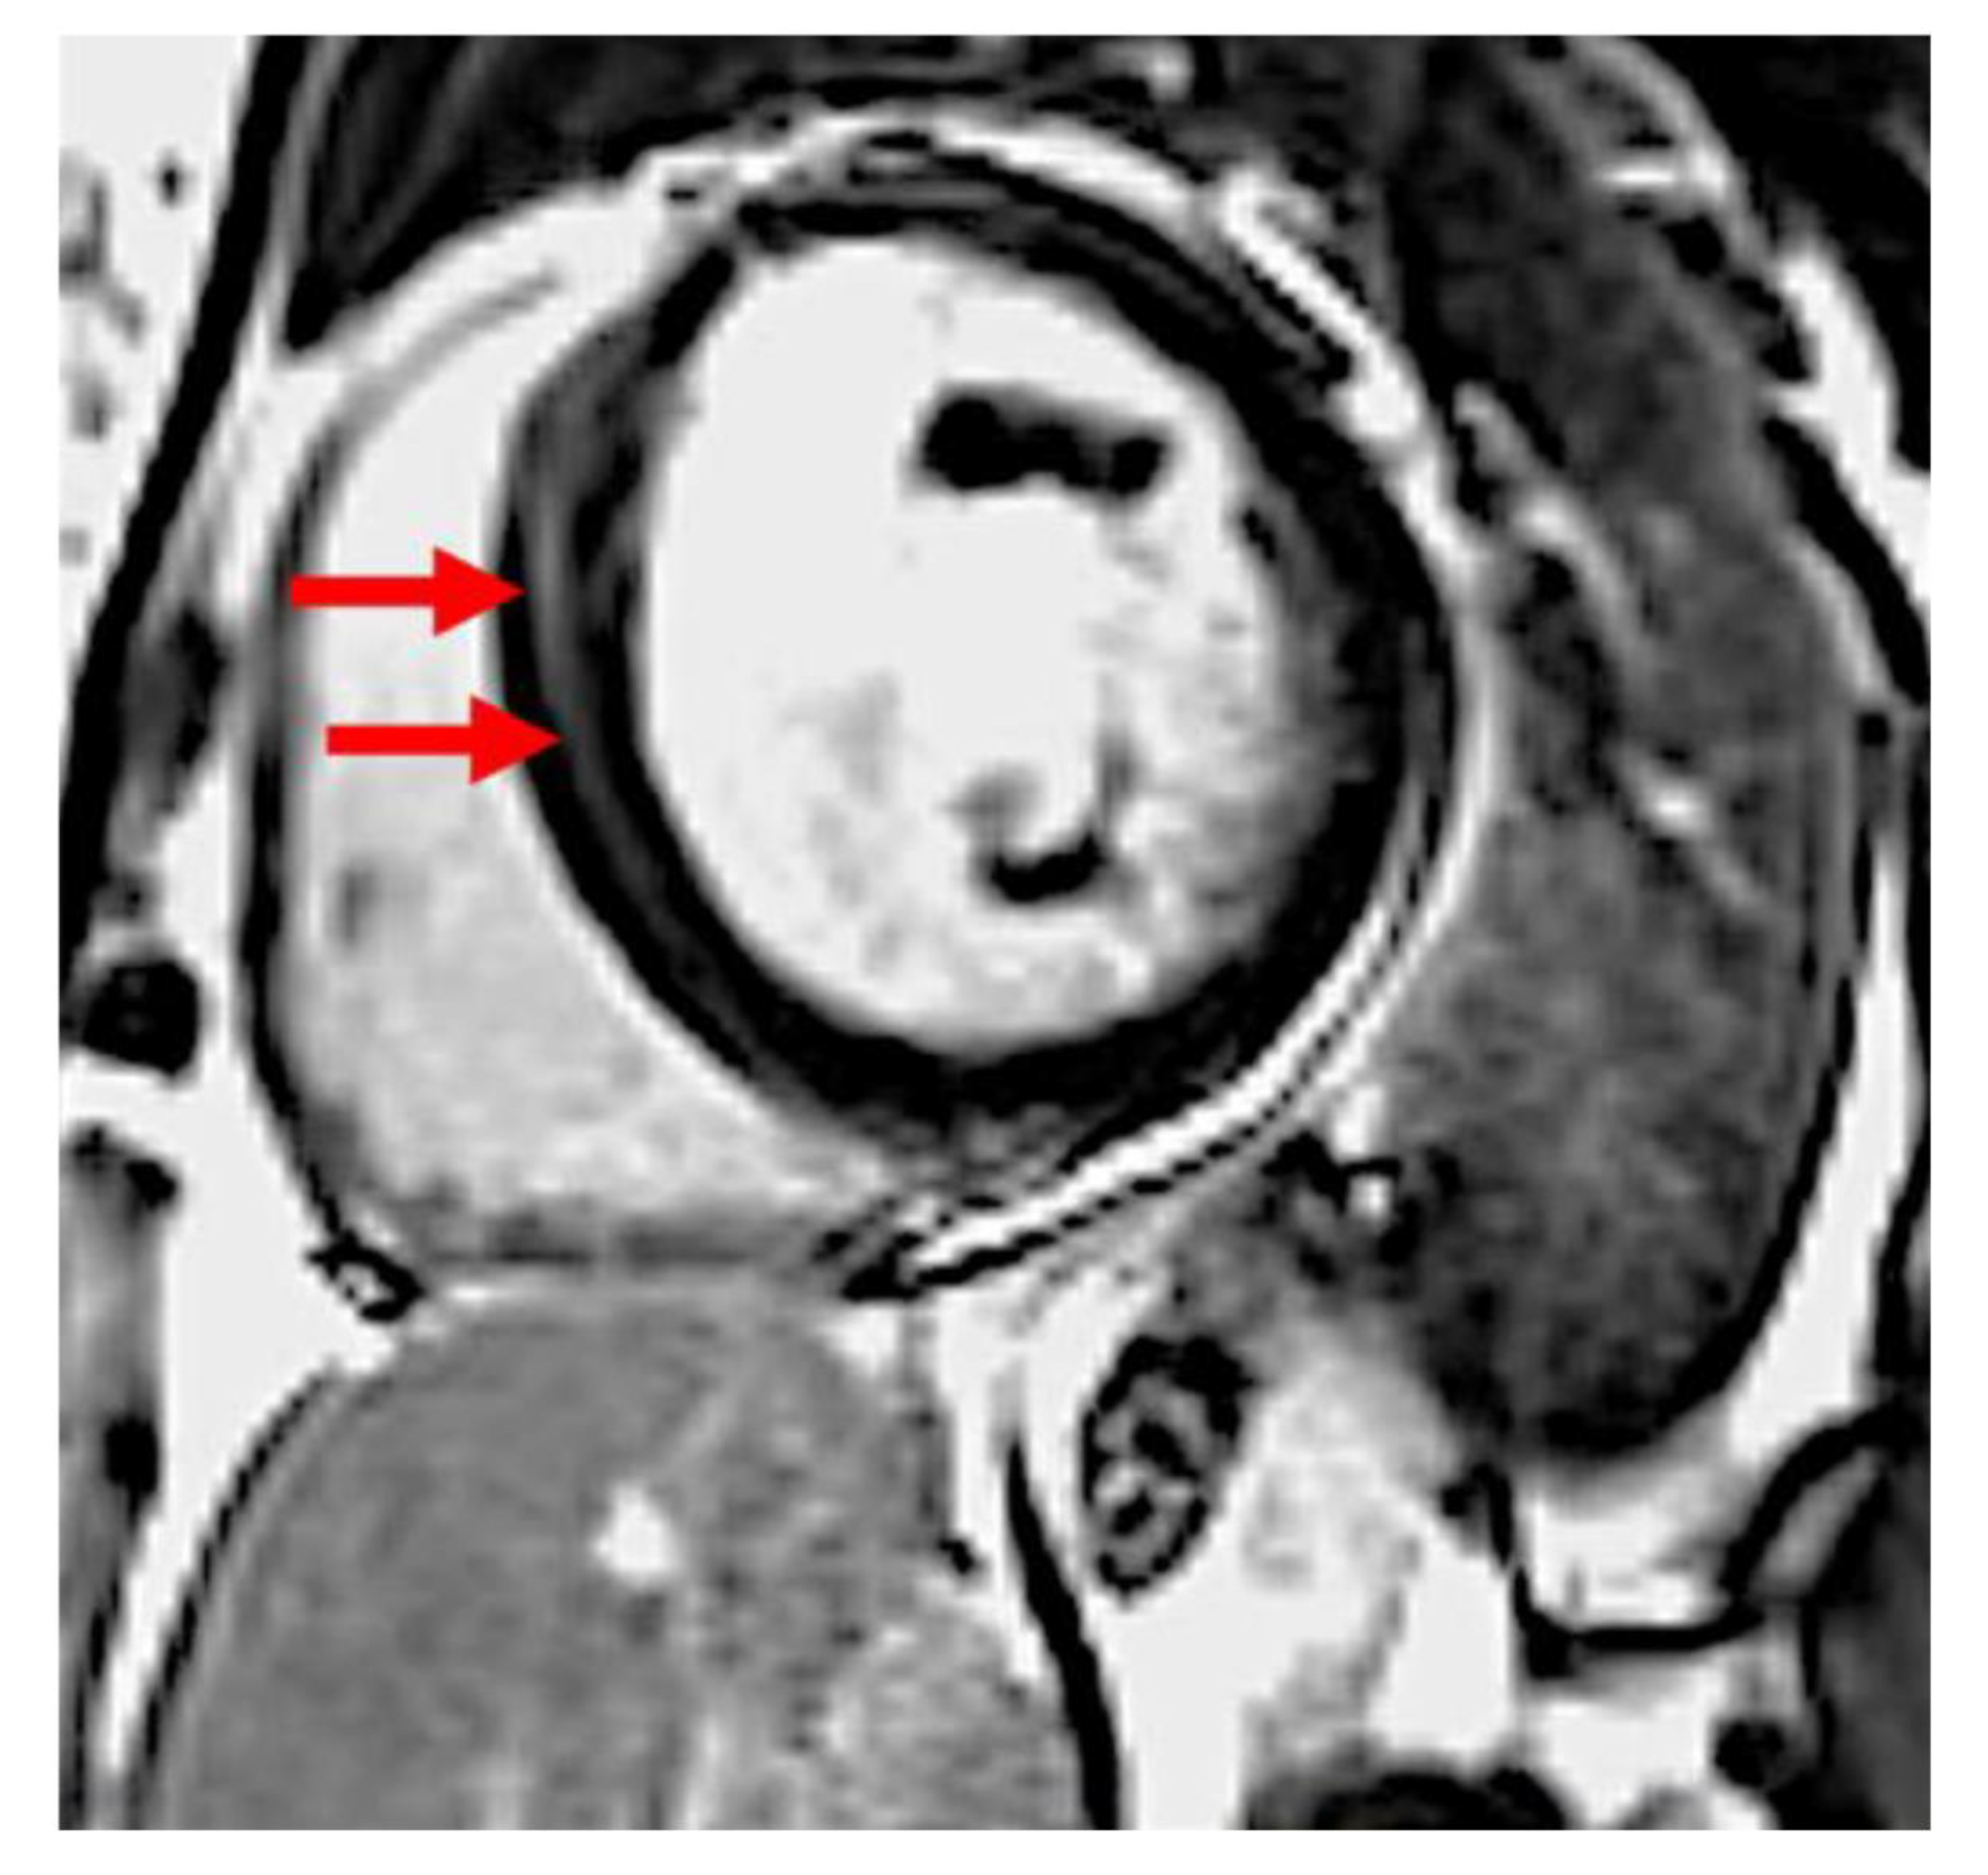

- Both PPCM and DCM female patients with LGE have more dilated and impaired left and right ventricles in comparison to patients without LGE on CMR imaging.

4.2. LV Fibrosis in PPCM